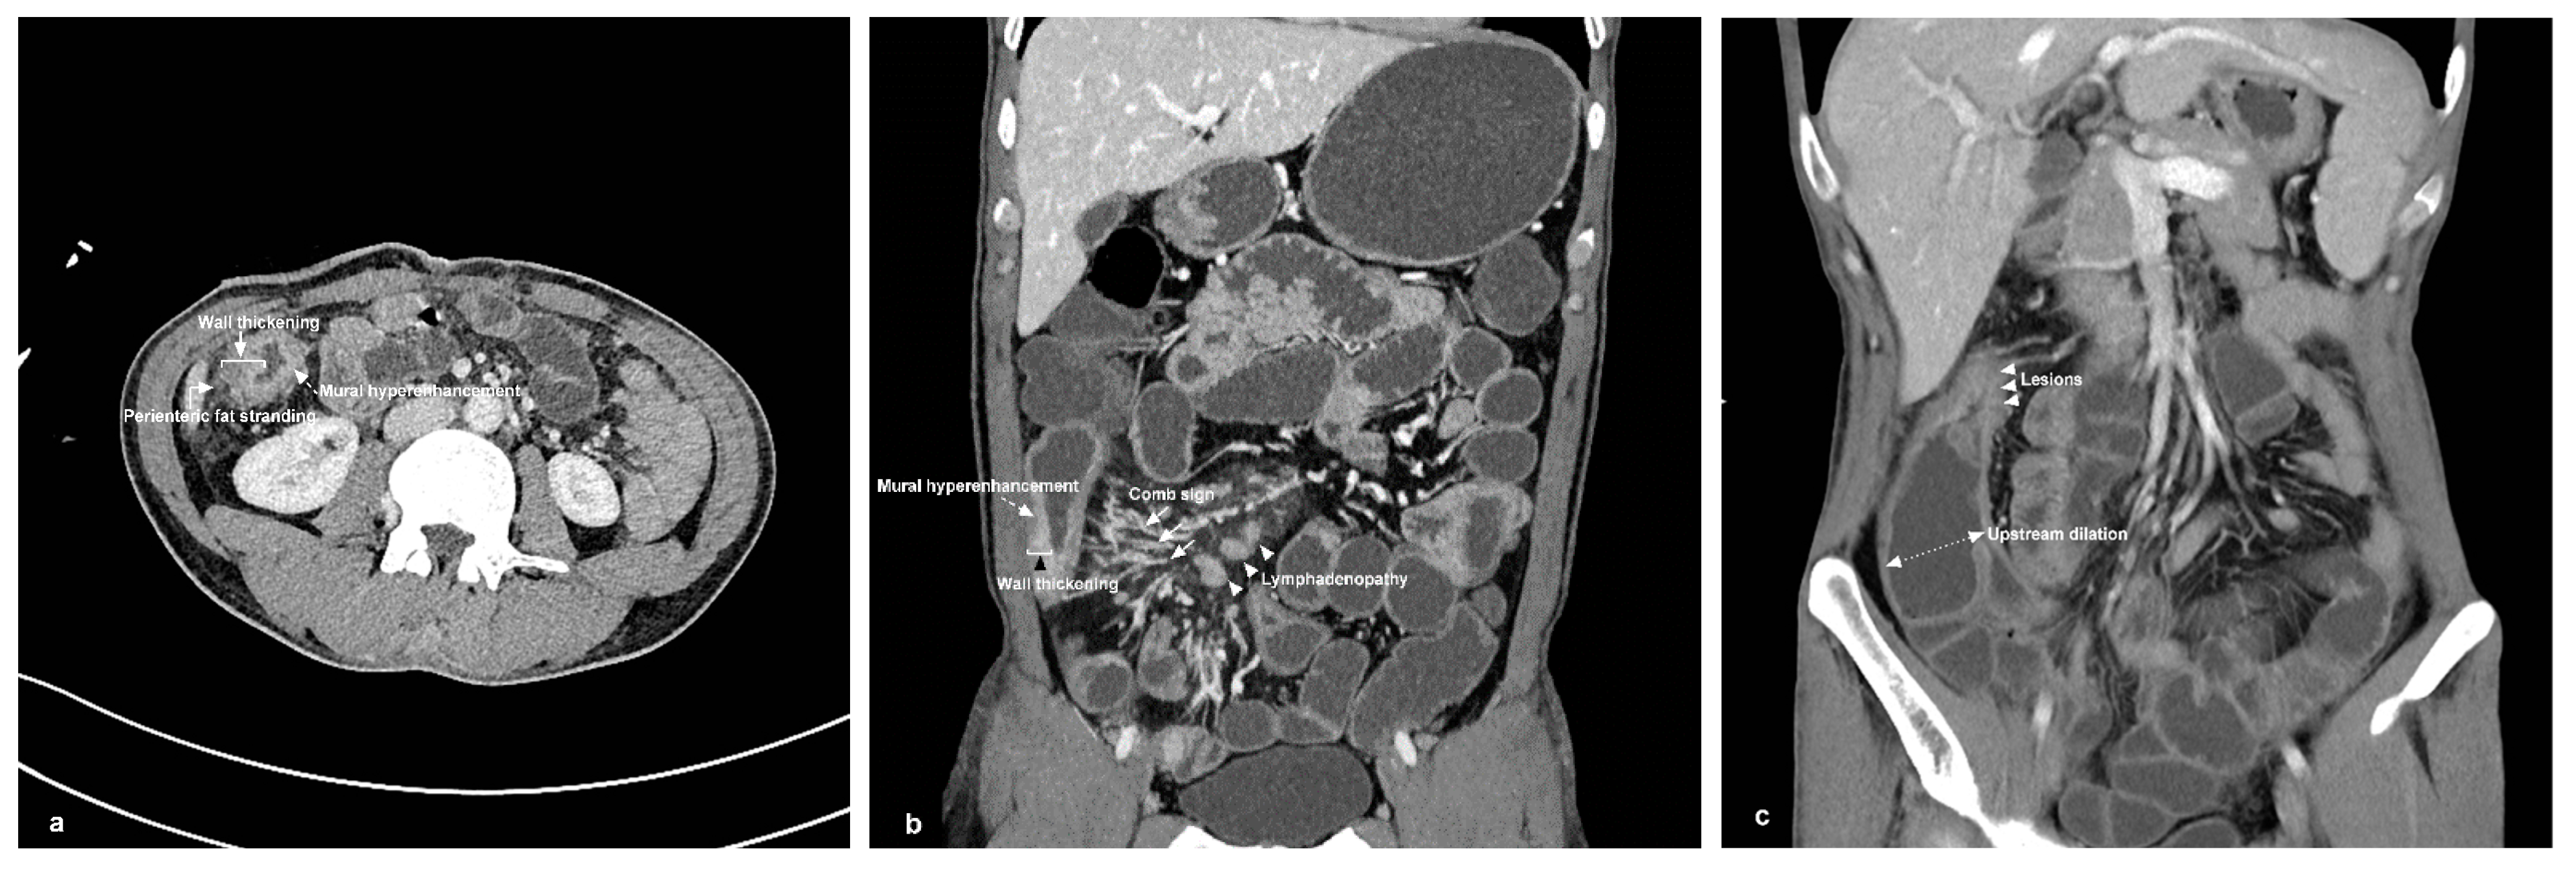

3.2. CTE Findings and Diagnostic Yield of CD Phenotypes

| CTE findings, n (%) | |||

| Bowel wall thickening | 19 (100.00) | 18 (100.00) | NS |

| Mural hyperenhancement | 19 (100.00) | 18 (100.00) | NS |

| Comb sign | 11 (57.89) | 4 (22.22) | 0.020 * |

| Lymphadenopathy | 13 (68.42) | 12 (66.67) | NS |

| Perienteric fat stranding | 19 (100) | 9 (50.00) | 0.000 * |

| Upstream dilation | 11 (57.89) | 8 (44.44) | NS |

| CTE score | 4.84 ± 0.77 | 3.83 ± 1.15 | 0.004 * |